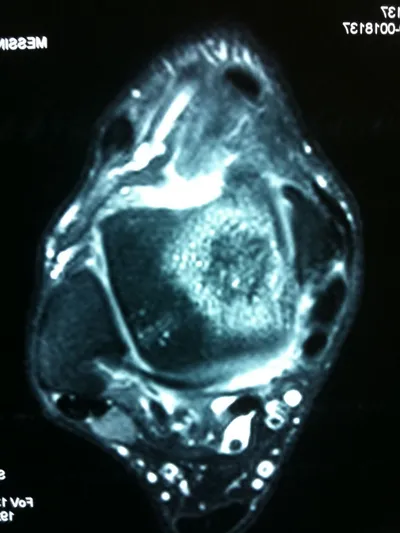

A series of intraop ankle arthroscopy pics of synovial chondromatosis with OCD talus and tibia and microfracture.

Pic of one of the nodules inside the ankle joint.